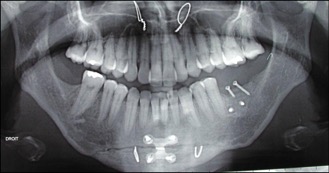

L’implant doit être entouré d’un os suffisant en qualité et en quantité.

Le problème le plus fréquent est un manque d’os, là où l’on souhaite poser un implant.